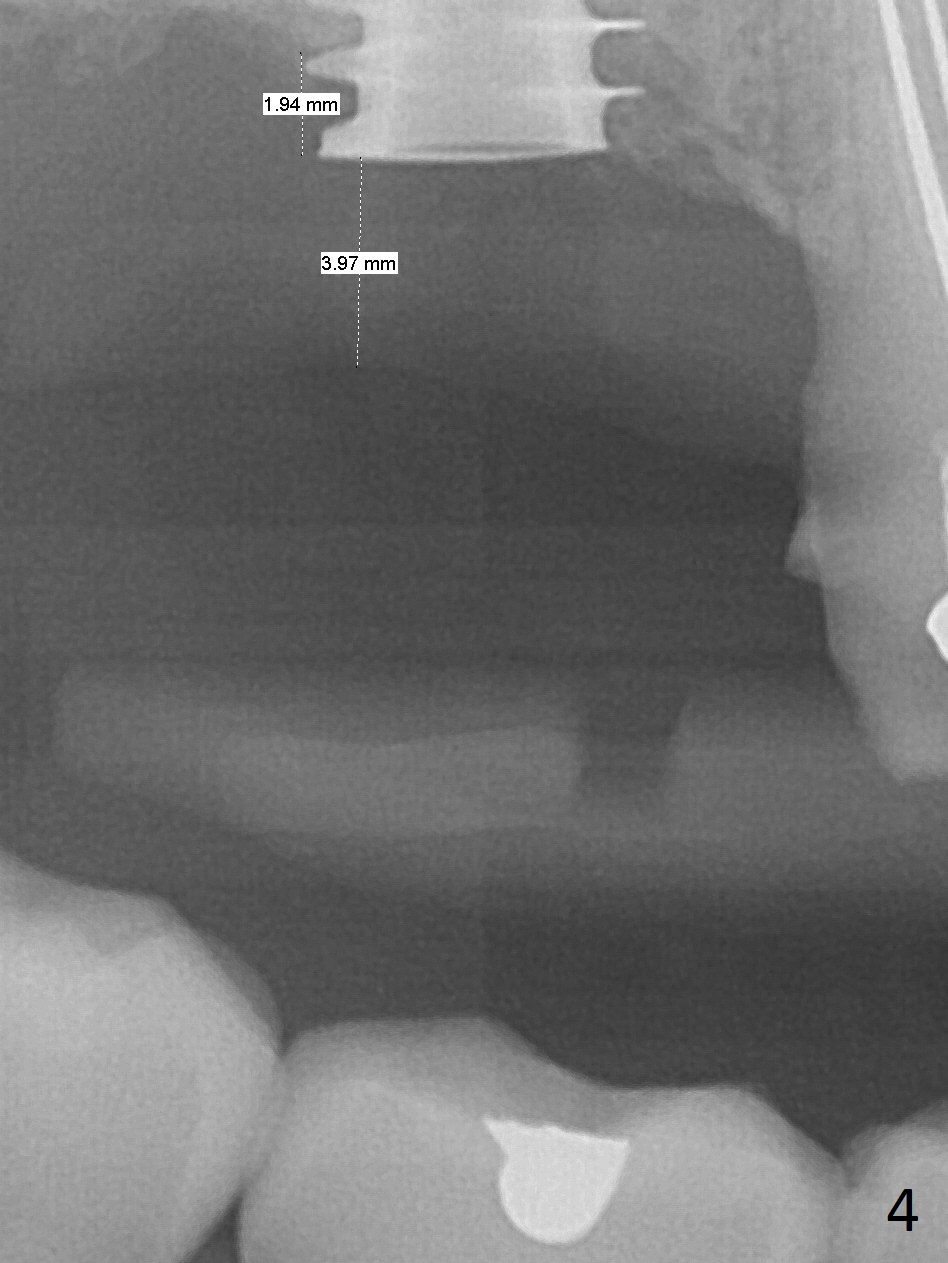

Since the ridge is wide at the site of #2, Magic Split is used for access (flapless) and bone expansion. The bone is so soft that there is no resistance until 4.3 mm Magic Expander is used for 9 mm (Fig.6). A 5 mm tap drill is stable (Fig.1), so are a 5.5x9 mm dummy implant (Fig.2) and a 6x9 mm IBS implant (Fig.3 (<: sinus lift)). In fact the distal thread is still supracrestal (Fig.4 (BW)). After additional 2 mm placement, the distal thread is subcrestal (Fig.5); the mesial margin of a 6.5x4(4) mm abutment is subgingival. A longer cuff (5 mm instead of 4 mm) is more favorable for future restoration. At present the abutment (Fig.7) as well as the tooth #3 with rugged surfaces is used to hold periodontal dressing in place. The abutment margin is completely subgingival 3 months postop (Fig.8 (white dashed line: gingival margin)). It appears that the implant is placed ~ 1 mm deeper than ideal (Fig.9). Diode laser is used for gingivectomy prior to impression. The abutment screw becomes loose 2 months post cementation. After retightening, occlusal equilibrium is conducted with 3 layers of articulating paper. Night guard is provided. The crown/abutment dislodges 1 year 2 months later. Since the gingiva is erythematous, a 6x7 mm healing abutment is placed (Fig.10). The implant seems to have been placed too deep and palatal. It appears that an abutment driver should be buried to prevent the screw re-loosening. Guided surgery should have been done.